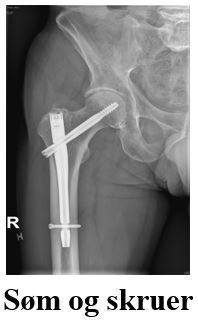

Der findes 3 forskellige typer hoftebrud. Vi har sat kryds ved den type brud du har.

Bruddet på- eller under lårbensknuden samles med en glideskrue eller et marvsøm og skruer. I sjældne tilfælde anvendes en anden operationsmetode.

Behandling af dit brud afhænger af bruddets type.

Der er i dit tilfælde anvendt den operationsform, som er afkrydset, se billeder på næste side. Forskellige brud i hoften behandles med skruer, med halvprotese, med glideskrue, med et marvsøm og skruer.